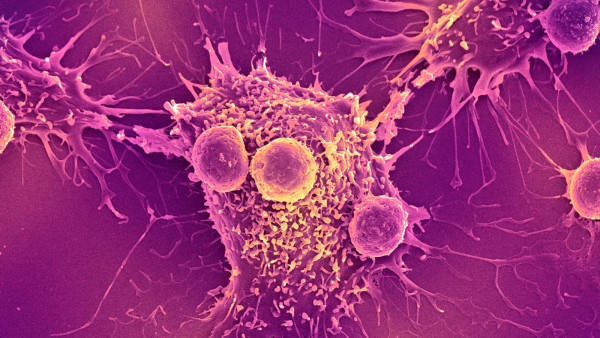

Нове дослідження показує, що тепер можливо розводити мишей із повністю розвиненою та функціональною імунною системою людини. (Зображення: Evgenyi_Eg via Getty Images)

Стикаючись з інфекцією, ці «гуманізовані» миші виробляють імунні клітини, що імітують структуру та різноманітність імунних клітин, що виробляються людьми. Дослідники виявили, що коли їм вводять хімічну речовину, яка викликає поширене запалення в організмі, у мишей розвивається варіант аутоімунного захворювання – вовчака, який дуже схожий на той, що спостерігається у людей.

Це не перші гуманізовані миші, яких коли-небудь виводили — лабораторні тварини є основними в дослідженнях, оскільки вони дозволяють вченим вивчати особливості імунної системи людини всередині живої тварини. Це корисно для перевірки безпеки та ефективності нових ліків, а також вакцин проти інфекційних захворювань, перш ніж їх випробовуватимуть на людях.

Після введення людського естрогену миші почали виробляти безліч людських імунних клітин. Серед них були Т-клітини, які безпосередньо атакують мікроби, та В-клітини, що виробляють антитіла, що знищують бактерії та допомагають позначити патогени для знищення.